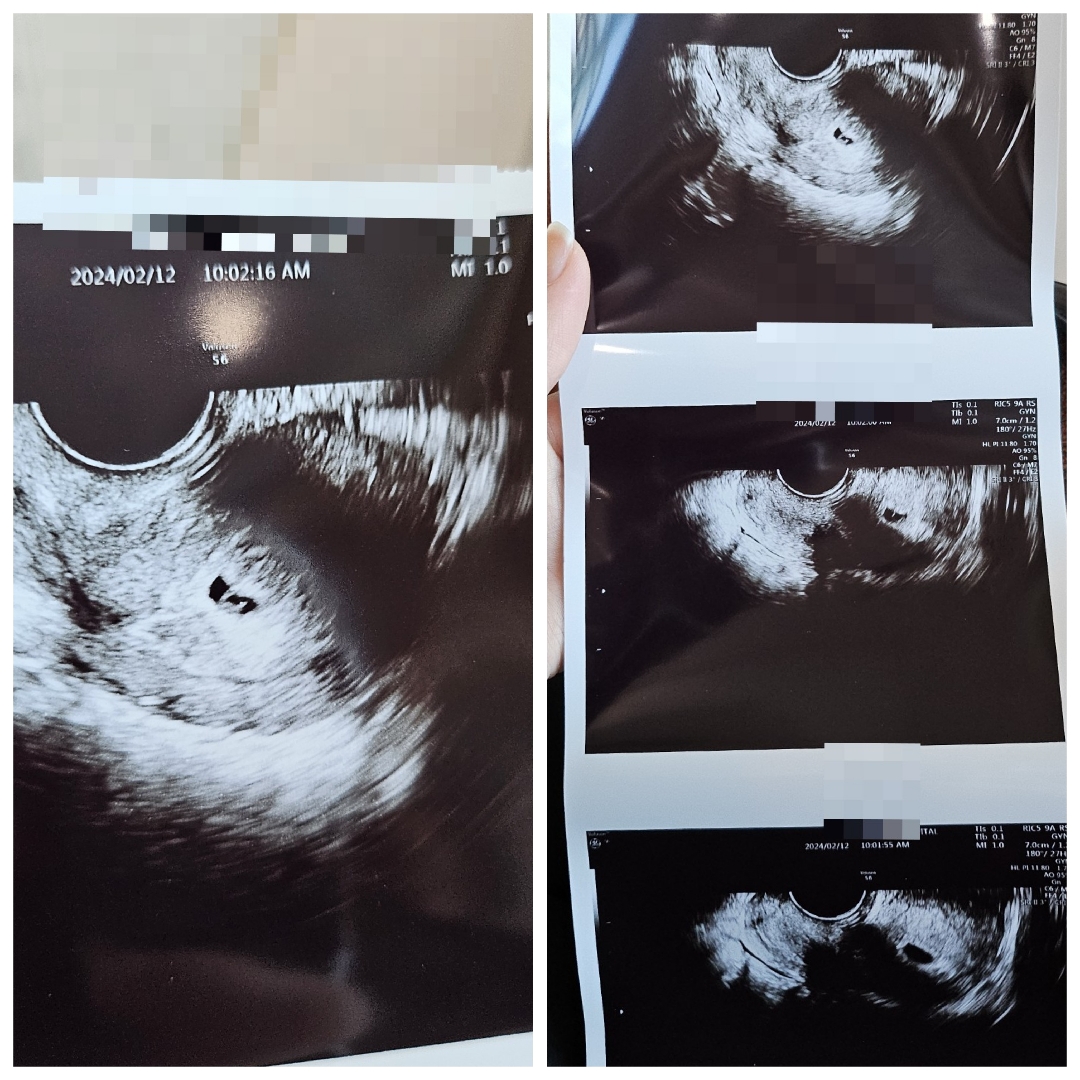

난황 보고 왔어요! 애기집 크기 봐주세요 ㅠㅠ

오늘 난황보고 왔는데 애기집이 너무 작은건가요? 선생님은 그런말은 없으셨지만 다른분들고 보면 제꺼 너무 작아 보이네요 ㅠㅠ

아기집 크기에 비해 난황이 크긴한데 쌤이 봐주시는 각도 따라 다르니~~ㅎㅎ 물이나 이온음료 많이 마시세용~~ㅎㅎ 원래는 아기집 크기 재주시는데 안재주나봐요?

감사합니다 🥰 네 안재주셨어요 ㅠㅠ 다음주 와서 심장소리 듣자고 하셨어요